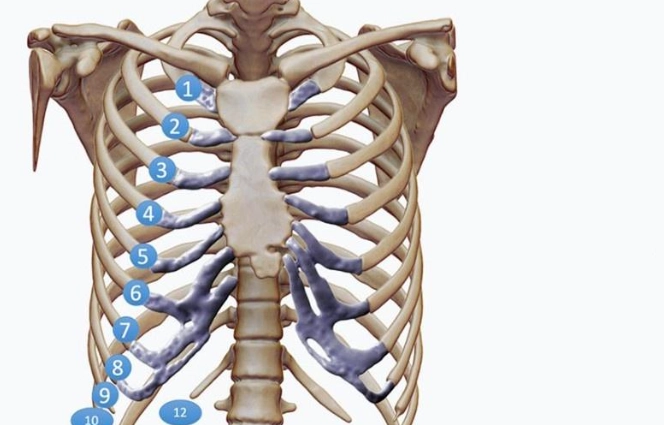

肋骨骨折後,身體會啟動自然的愈合過程,包括炎症期、修復期和重塑期。這段期間,營養攝取直接影響骨骼的再生能力。如果吃了不該吃的東西,可能會干擾這些階段,導致恢復延遲或併發症。例如,高鹽分食物會引起水腫,增加胸腔壓力,讓呼吸都變得更痛苦。而辛辣食物則可能刺激神經,加劇疼痛感。

我記得醫生告訴我,骨折愈合需要大量的蛋白質、鈣質和維生素D。這些營養素能促進骨痂形成,讓斷裂的肋骨慢慢接合。反之,如果攝取過多禁忌食物,就像在傷口上撒鹽,不僅無助恢復,還可能讓情況惡化。所以,肋骨骨折不能吃什麼,絕對不是小事,它關係到整個恢復期的舒適度和效率。